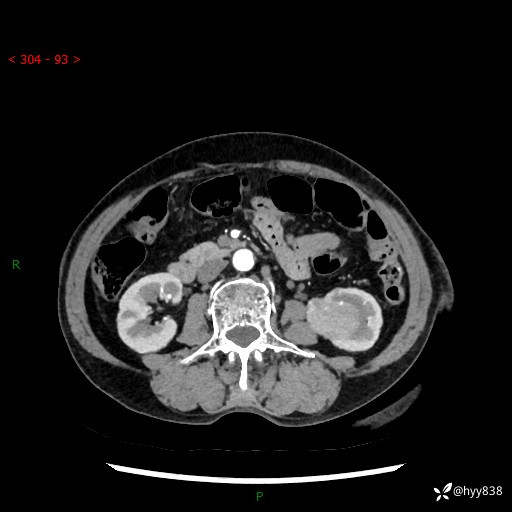

72岁/女,检查发现左肾占位1天。为了满足诊断,常规四期后,又加了延迟期-结果公布~

【患者信息】:72岁/女

【主诉】:检查发现左肾占位1天

【现病史及既往史】:患者于1天前检查发现左肾占位,无畏寒发热,无咳嗽咳痰,无腰腹部疼痛不适,无肉眼血尿、无尿频尿急症状,起病来,患者未行特殊治疗,为求进一步诊治,门诊以"左肾占位"收治入院。 发病来患者精神、饮食、睡眠良好,小便如上,大便正常,体重无明显变化。

【检查】:肾脏CT平扫+增强